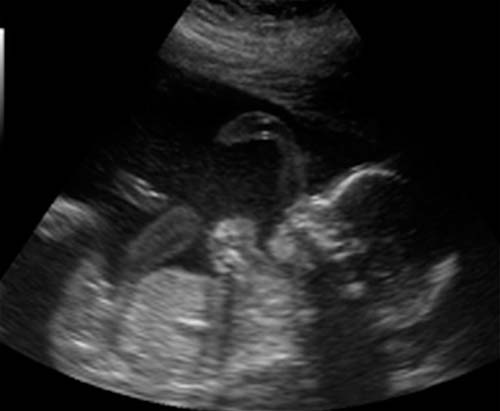

Foto de ultrassom com 21 semanas (clique para ampliar):

Com uma localização bem-sucedida do feto, você pode descobrir o sexo do bebê. Mas o futuro menino ou menina às vezes pode "esconder" até o nascimento.

Se você não fez um ultrassom no segundo trimestre, ele será indicado. Um médico especialista verificará as principais dimensões do corpo e membros do feto, a condição dos órgãos internos e vários outros indicadores. A placenta não será menos minuciosamente examinada.